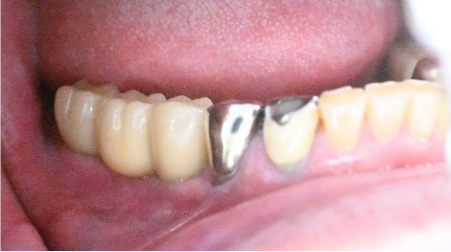

男性 Hさん 60代 (インプラント)

主訴

右上の犬歯の歯茎が腫れている。

治療内容

歯根が数か所破折していましたので、抜歯せざるを得ませんでした。抜歯後、インプラントを埋入しました。

所感

2020年4月に右上前歯から左上奥歯までのインプラント治療(5本インプラント埋入)をされていましたので、今回も抜歯後、インプラント治療を希望されました。

この症例は、X-Guideを使って埋入しました。理想的なポジションに埋入できています。

インプラント1本:¥363,000(税込)